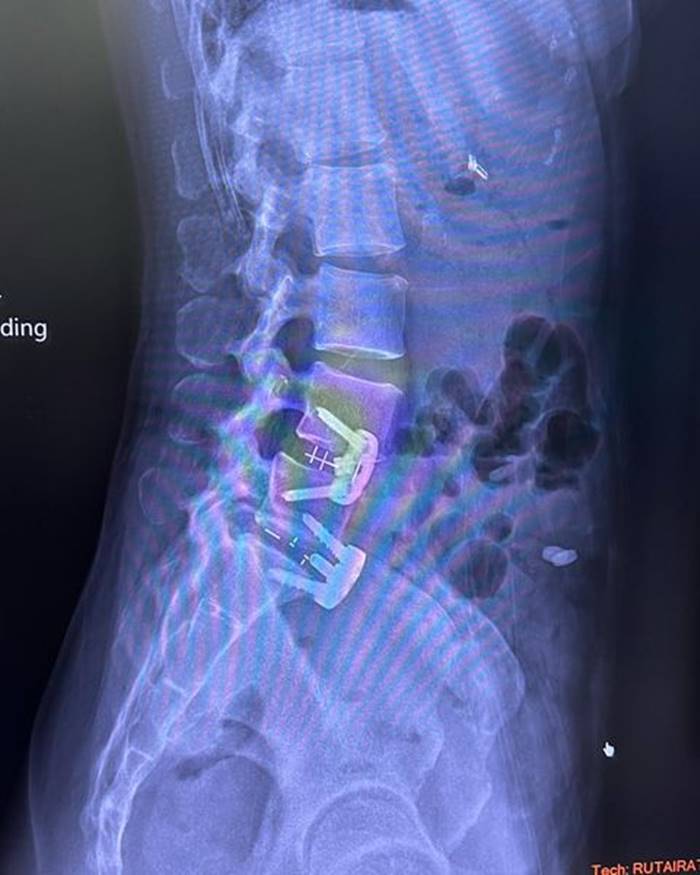

โดยเมื่อวันที่ 28 กรกฎาคม 2565 มาดามหนุ่ย ได้โพสต์ภาพเอกซเรย์กระดูกที่ถูกใส่เหล็ก พร้อมข้อความว่า "อยากขอเตือนเพื่อน ๆ นะคะ ว่าถ้าออกกำลังท่าไหนแล้วรู้ตัวว่าไม่ไหวก็ให้บอก trainer ค่ะ อย่าฝืนทำ เพราะลงท้ายอาจจะต้องผ่าตัดแบบหนุ่ย.. trainer ให้ทำ squat ที่หนุ่ยก็หันไปบอกแล้วว่าหนักไปทำไม่ได้เค้าก็ยังให้ทำ ผลคือหมอนรองกระดูกปลิ้น ต้องผ่าตัดใส่เหล็กตามภาพเลยค่ะ..ตอนนี้ก็ต้อง slowlife ไป 4-5 เดือน"